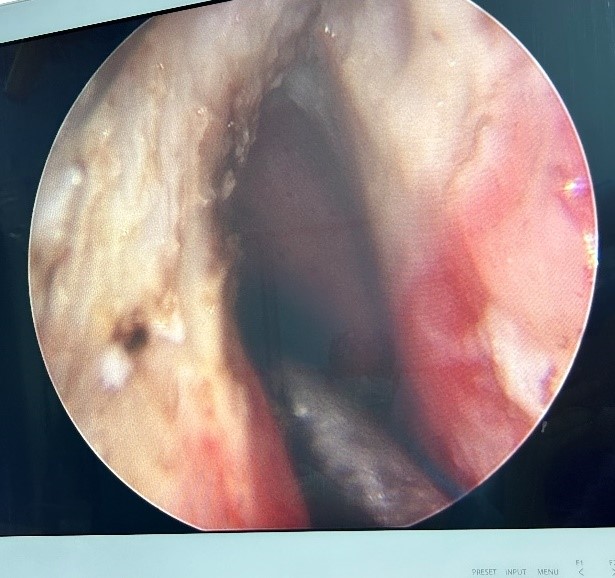

手术室内,气氛紧张而凝重。当支气管镜顺利进入,眼前的景象令人揪心:声门处管腔狭窄程度高达95%,巨大的白色肿物如同巨石般堵塞其中,表面光滑却质地坚硬。医疗团队沉着应对,先予圈套器多次圈套电切治疗,同时进行活检,样本送检常规病理。在精细操作下,声门得以部分暴露。在李健主任带领下的麻醉团队支持配合下,气管插管辅助通气。后续耳鼻喉科宋升桥主任凭借其深厚的专业功底,在支撑喉内镜下行喉部肿瘤等离子切除术。每一次操作都精准无误,每一个步骤都紧密衔接。在团队的共同努力下,肿物被逐步、分段切除,声带及喉室得以充分暴露,术后喉空间完全开放,管腔恢复通畅,如同被疏通的河道,重新恢复了生机,同时,凭借团队精湛的医术与充分完善的术前准备,避免气管切开带来的痛苦。术中患者生命体征始终保持稳定,术后患者呼吸明显顺畅,当晚便酣然入睡,目前患者正在住院恢复当中。